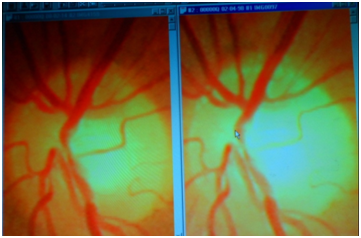

With X-Ray coronary angiography not only is the procedure itself complicated, inaccurate and unrepeatable because of the radiation burden, but there is an incidence of 2% of new cancers that cardiologists rarely mention. There would seem to be little justification for X-Rays for what is a suspected metabolic deficiency and now, even less for surgery for an antioxidant deficiency. In the “normal” course of events over a period of 16years, from 1998 to 2014 as shown above, the expected change would be from Left to Right as atherosclerosis develops, circulation deteriorates and death slowly approaches. Here we see the deterioration nor only arrested but reversed. All the vessels are functioning better, neural recovery is evident. Blood flow is greatly improved and if the peripheral vasculature were shown it would be seen to be better perfused with reduced tortuosity of the vessels. The images are of the retinae belonging to author Bush´s older son born in 1956. His fundi now resemble more what we might expect to see in a very healthy 20year old, and definitely better than we would expect to find in a sportsman engaged in competitive events with corresponding stress (Figure 3).

Figure 3 X-Ray coronary Angiography.